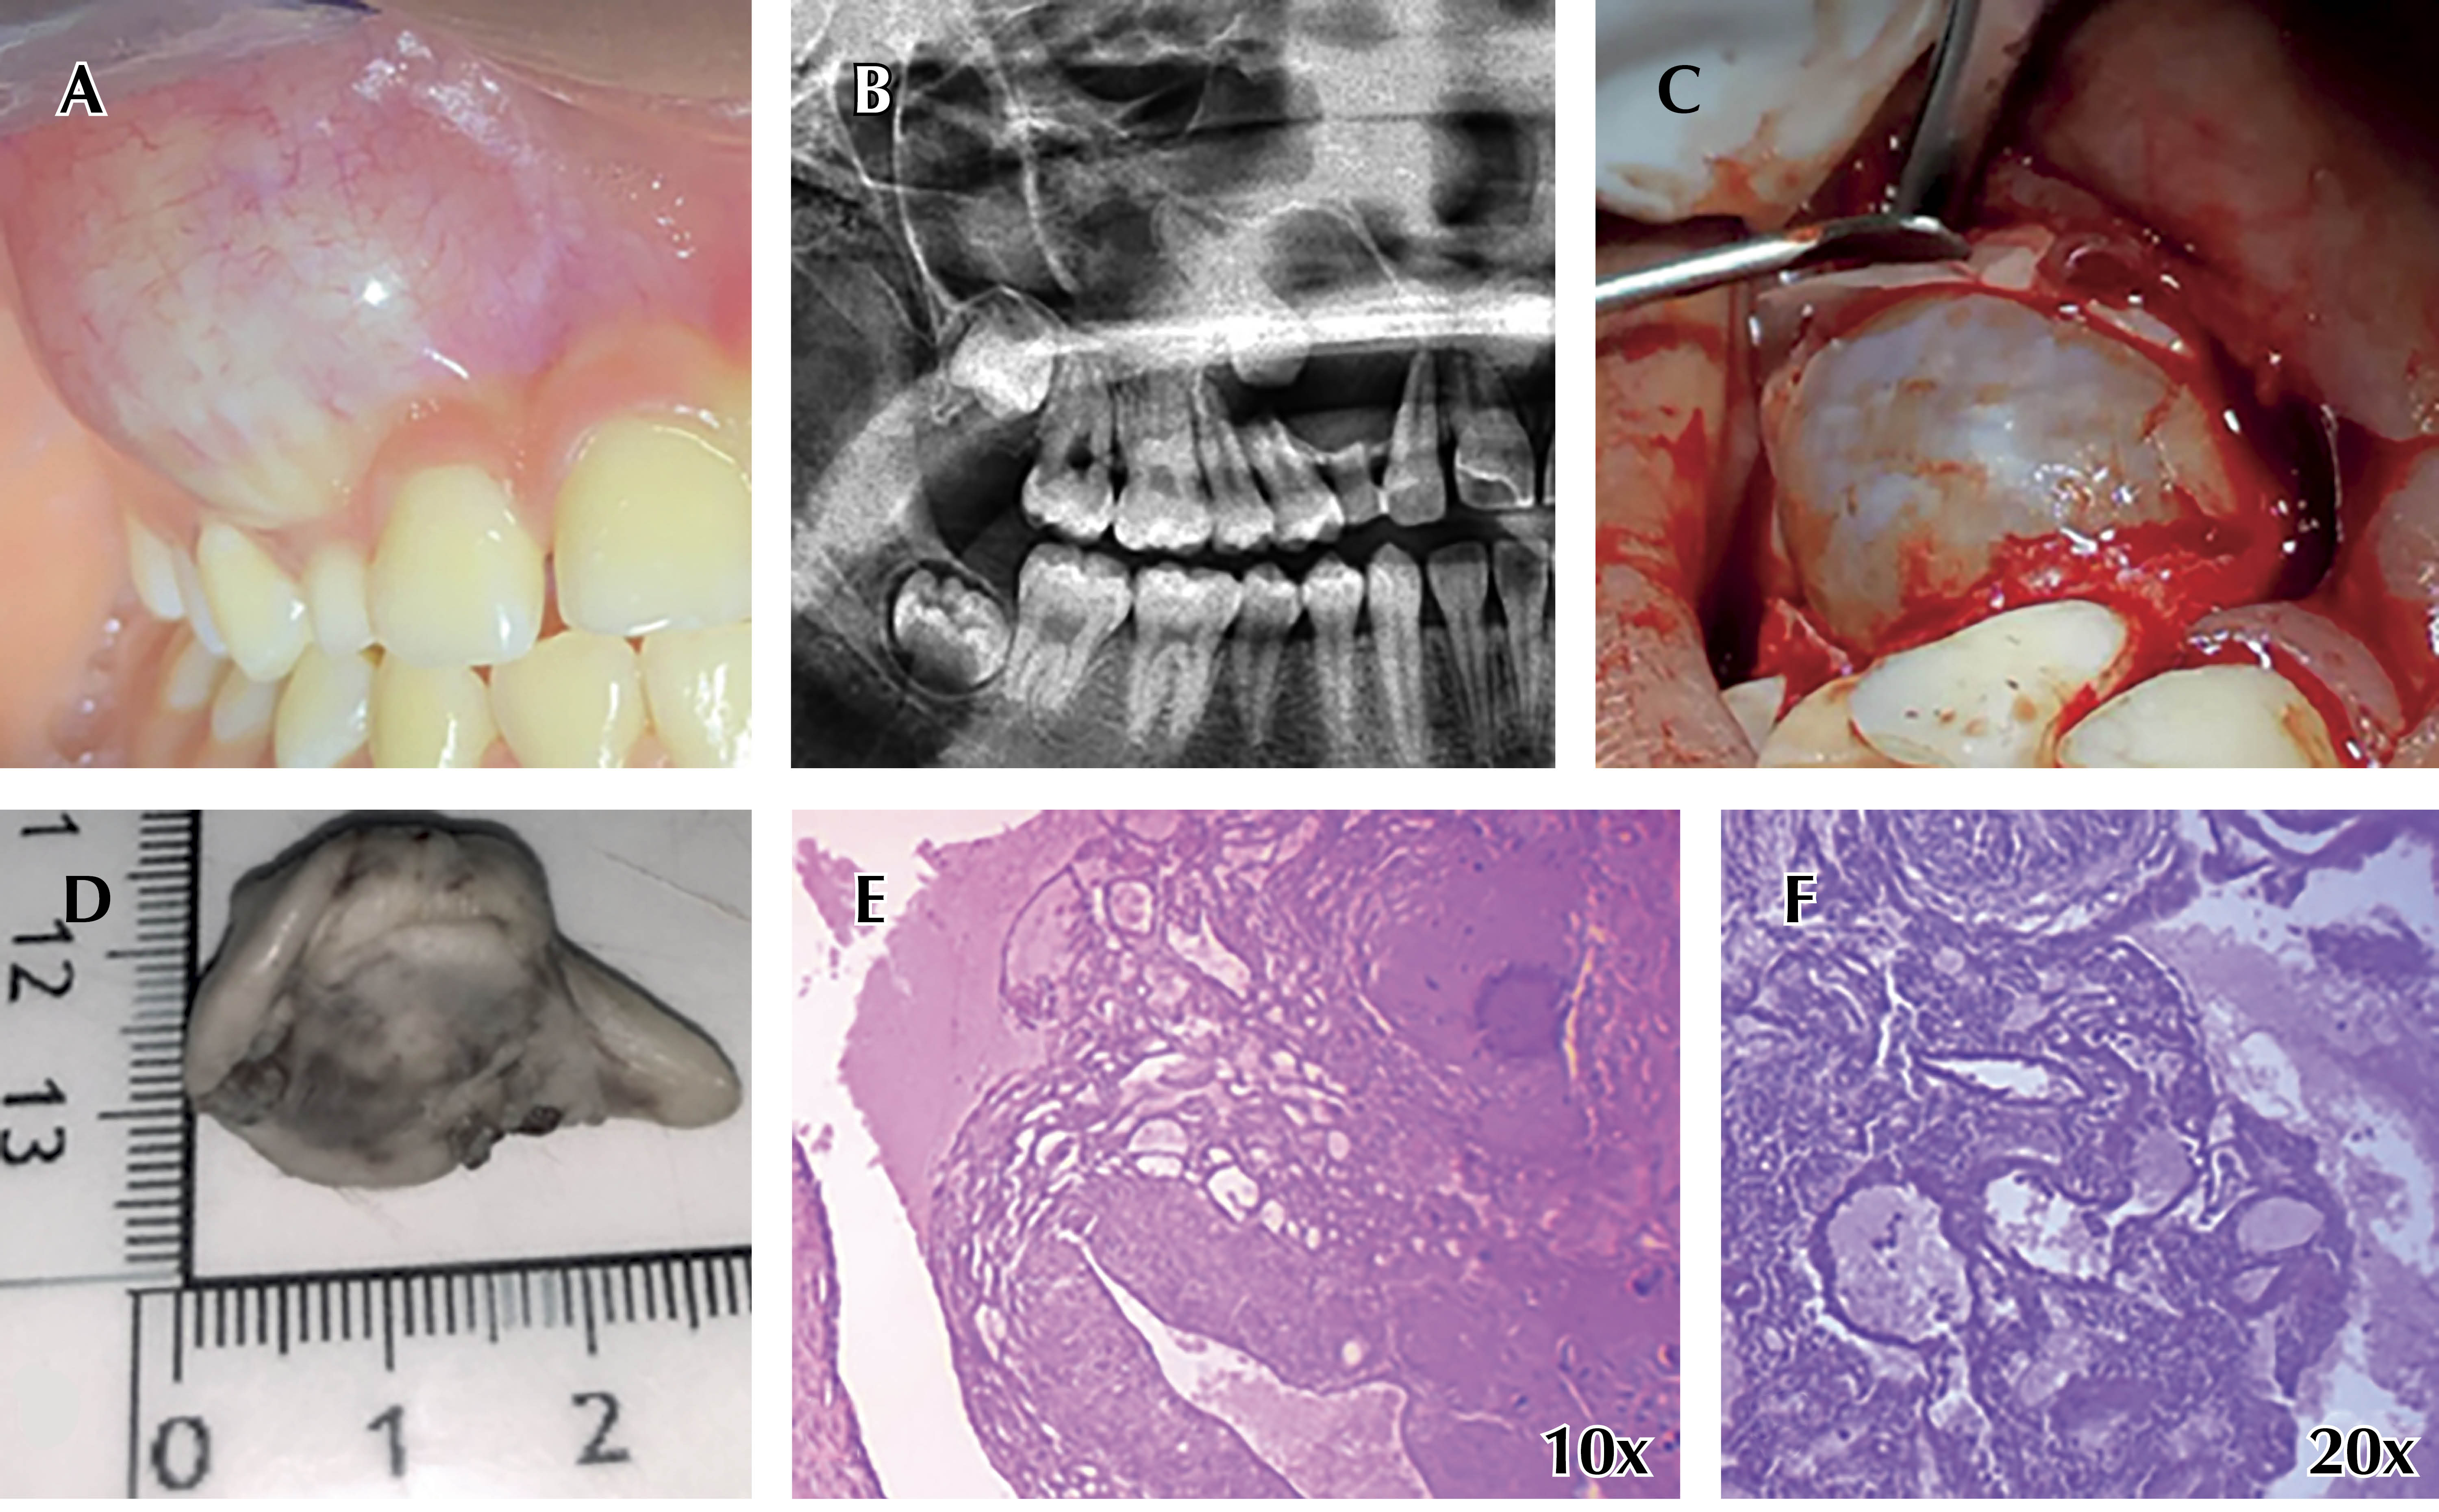

Caso 2: mujer de 33 años, con asimetría facial de crecimiento lento asintomático, la imagen es mixta bien delimitada con borde esclerótico, macroscópicamente se observan las calcificaciones y la histopatología (Figura 3).

Caso 3: mujer de 18 años con aumento de volumen maxilar, de crecimiento, asintomático, la imagen es mixta bien delimitada (Figura 4).